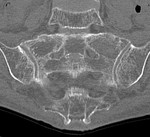

[画像診断]仙骨脆弱性骨折について【初期研修医と学ぶ】 2010-08-20